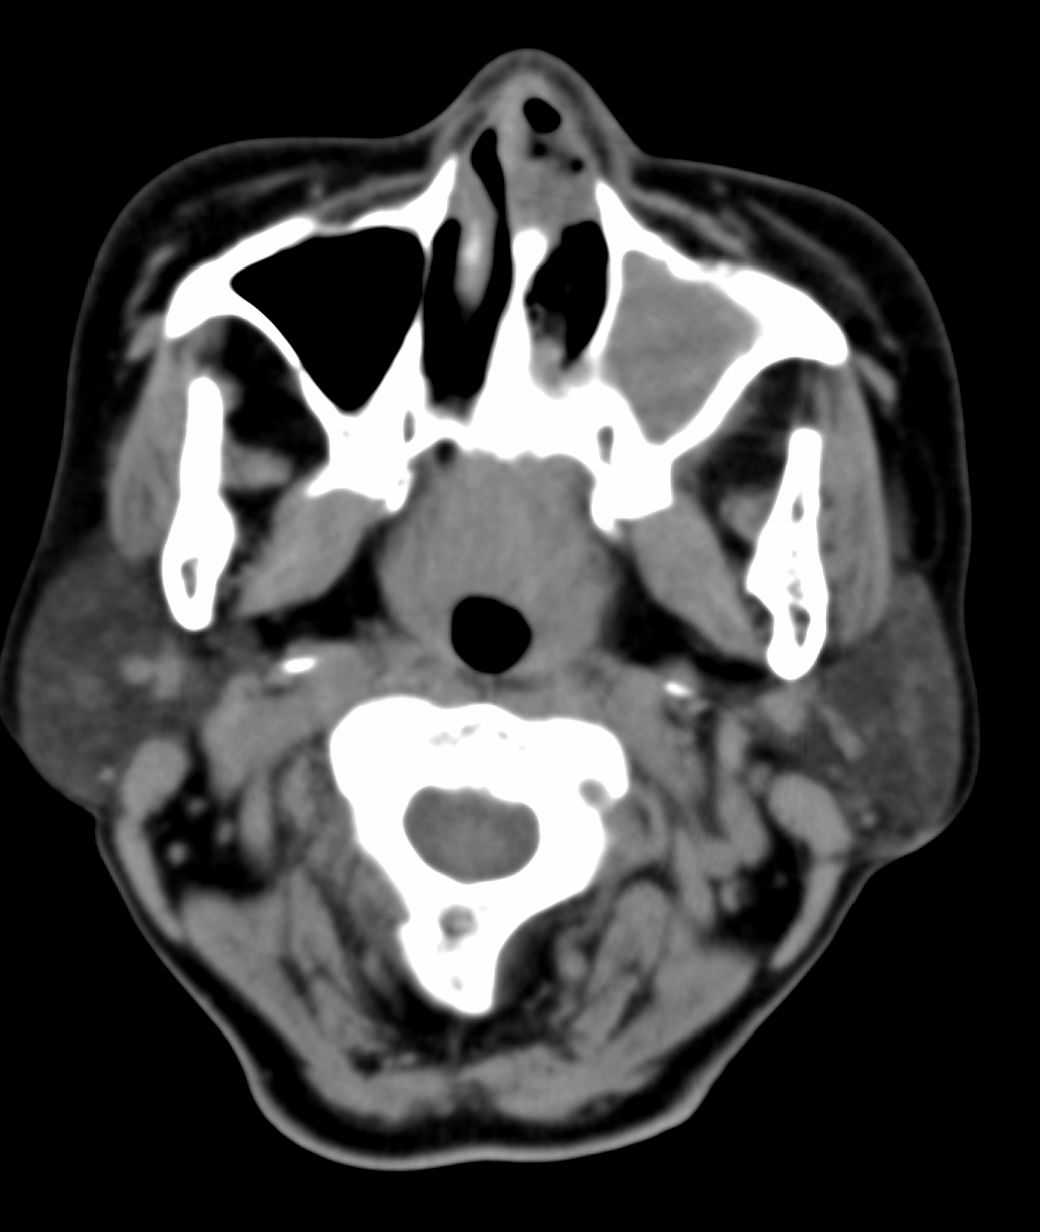

女,69岁。鼻出血2月多。(会诊病史就这样简单)鼻副窦ct检查如下:

左侧鼻腔及上颌窦见软组织块影,左侧上颌窦腔扩大,骨质吸收,右侧上颌窦见半圆形软组织密度影,鼻中隔向右侧弯曲,左侧鼻和鼻窦内翻型乳头状瘤可能性大,建议增强。

左侧上颌窦及鼻腔内见软组织密度影,其内密度不均匀,见斑片状高密度影,右侧上颌窦腔明显扩大,窦壁吸收变薄,鼻中隔右偏,右侧上颌窦见一半圆形软组织密度影,边界清楚,其内密度均匀。诊断,1、左侧鼻腔及上颌窦内翻乳头状瘤可能性大,上颌窦癌,息肉及霉菌性上颌窦炎待除外。2、右侧上颌窦粘膜下囊肿。

1)考虑左侧上颌窦内翻乳突状瘤突入左侧鼻腔。2)副鼻窦炎,右侧上颌窦黏膜下囊肿。

病理:霉菌性左侧上颌窦炎伴左侧上颌窦纤维组织增生。

窦腔密度不均匀增高,无明显钙化征象,后外侧及内侧窦壁膨胀明显,局部破坏消失,筛窦受累及,但双侧对比发现左侧窦壁骨质有硬化增白现象,这可能是支持左侧霉菌性上颌窦炎的主要依据点。